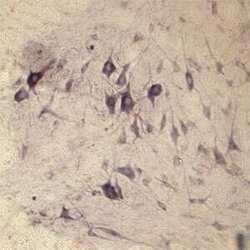

OSS00040W IHC

Full details

Method:

Other validation